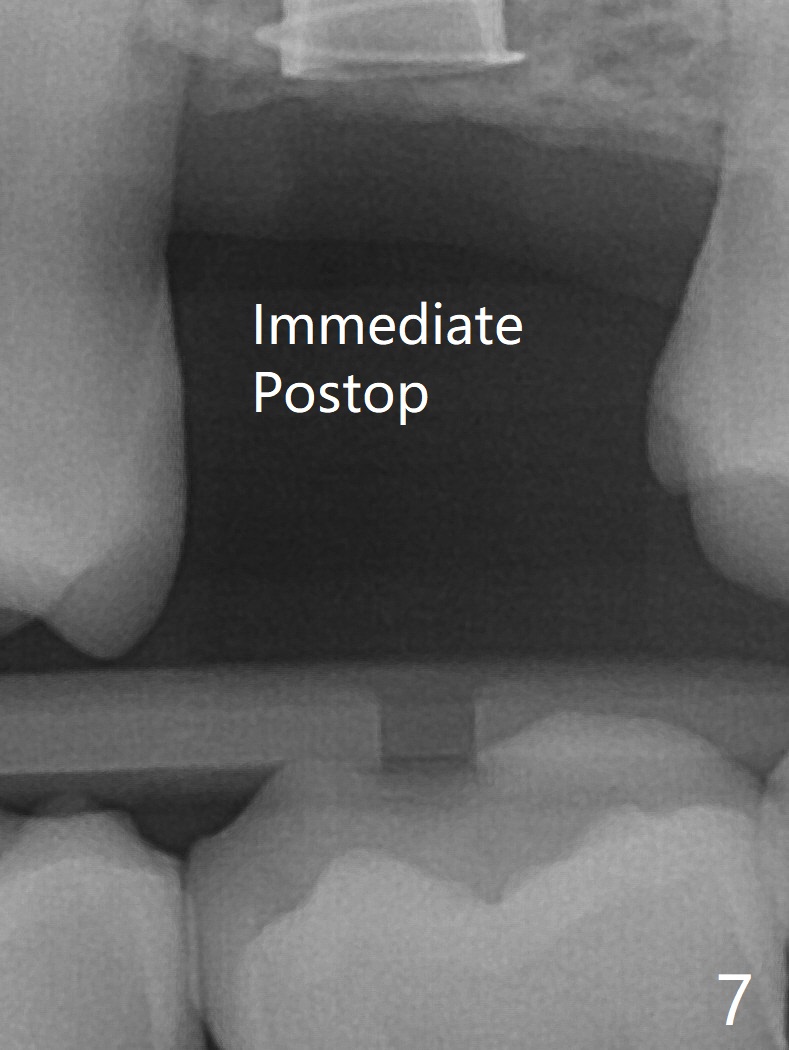

66岁男右上,左上7导板延期种植(足够角化龈,使用环形切刀),都提升,但是前者未植骨(图一,二(骨高度多,进入上颌窦少)),后者植骨(图六(*),七),由于扭力低(小于15Ncm),放置愈合螺帽和剪成圆形六个月胶原膜,使用牙周胶水(图三,八),之后不再放置牙周敷料。当钻头接近左侧上颌窦底板时,放置骨粉(图四-六:*),使用报废植体(图四,五)和正式植体(图六)将骨粉推入上颌窦。术后病人抱怨食物撞击伤口疼痛,即刻修复减少术后疼痛。术后5个月没有骨质吸收,基台完全就位(图十一,二)。